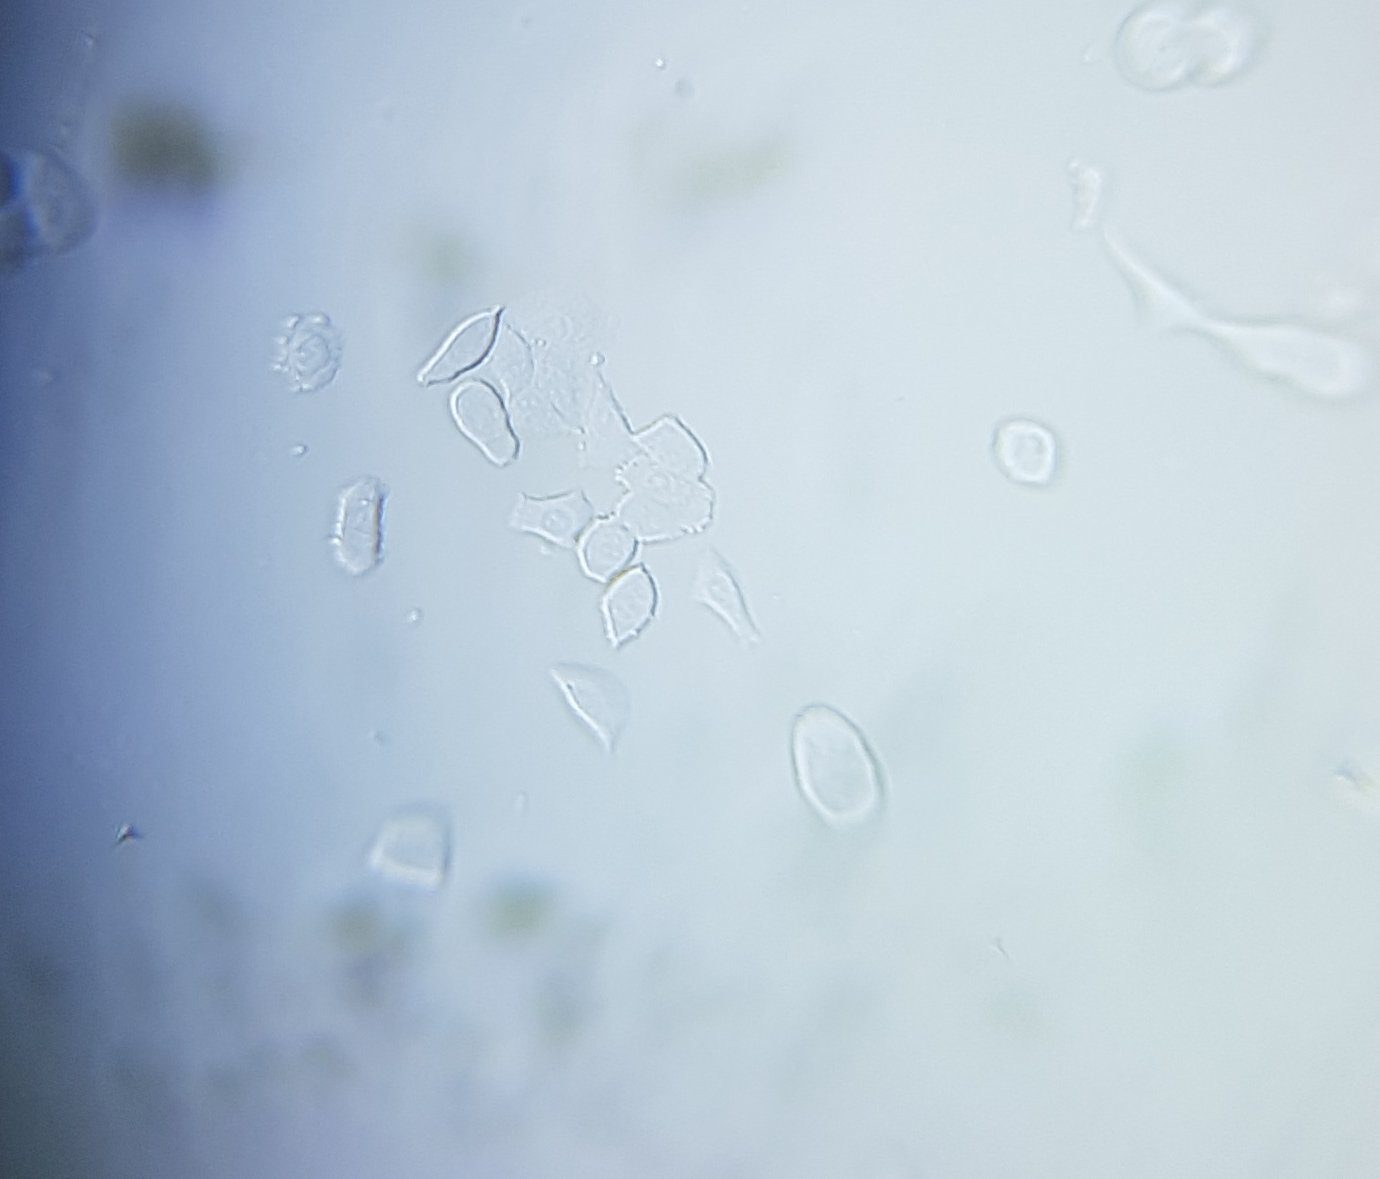

Thumbnail for Cancer cells

Cancer cells

0 Applause0 Comments

8y